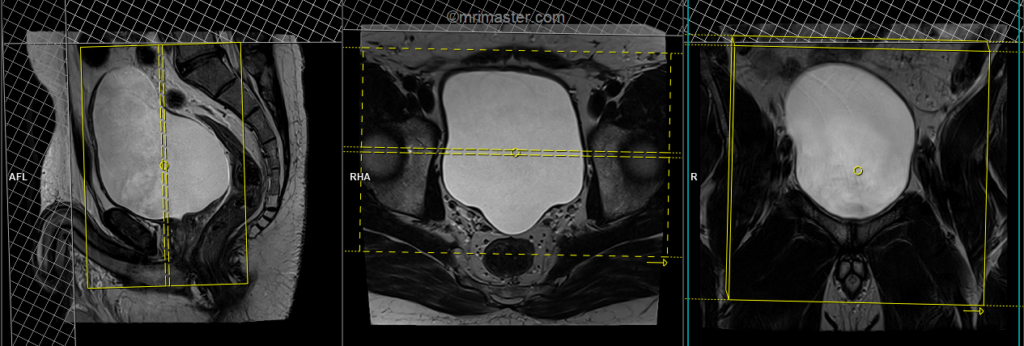

T2 tse sagittal 3mm SFOV

Plan the sagittal slices on the coronal plane, angling the positioning block parallel to the urinary bladder (i.e., parallel to the pubic symphysis and median sacral crest). Check the positioning block in the other two planes. An appropriate angle must be given in the axial plane (parallel to the line along the linea alba and the median sacral crest). Slices should be sufficient to cover the entire urinary bladder from the right acetabular rim to the left acetabular rim. Using a saturation band above and in front of the sagittal block will help reduce artifacts caused by breathing and peristalsis.

TR 4000-5000 | TE 100-120 | SLICE 3 MM | FLIP 130-150 | PHASE A>P | MATRIX 320X320 | FOV 200-250 | GAP 10% | NEX(AVRAGE) 2 |

T2 tse axial 3mm SFOV

Plan the axial slices on the sagittal plane and angle the positioning block horizontally across the urinary bladder. Check the positioning block in the other two planes. An appropriate angle must be given in the coronal plane, horizontally across the urinary bladder. Slices should be sufficient to cover the urinary bladder from L1 down to two slices below the symphysis pubis. To reduce artifacts from breathing and peristalsis, consider using a saturation band above and in front of the axial block.

TR 4000-6000 | TE 100-120 | SLICE 3 MM | FLIP 130-150 | PHASE R>L | MATRIX 320X320 | FOV 200-250 | GAP 10% | NEX(AVRAGE) 2 |

T2 tse coronal 3mm SFOV

Plan the coronal slices on the sagittal plane; angle the positioning block vertically through the urinary bladder. Check the positioning block in the other two planes. An appropriate angle must be given in the axial plane (parallel to the right and left hip joints). Slices must be sufficient to cover the entire urinary bladder from the anterior abdominal wall up to the rectum. Using a saturation band above and in front of the coronal block will help reduce artifacts from breathing and peristalsis.

TR 4000-5000 | TE 100-120 | SLICE 3 MM | FLIP 130-150 | PHASE R>L | MATRIX 320X256 | FOV 200-250 | GAP 10% | NEX(AVRAGE) 2 |